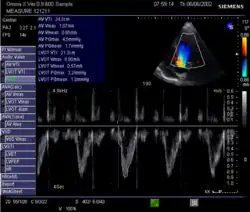

- In der Echokardiografie: Einfach ist es aus dem Schlagvolumen und der Herzfrequenz berechenbar: HMV = Herzfrequenz × Schlagvolumen. Das Schlagvolumen und die Herzfrequenz können aus der Echokardiografie abgeschätzt werden. Der Durchmesser des linksventrikulären Ausflusstraktes (LVOT) wird im 2D-Bild gemessen und daraus wird mit Hilfe der Kreisformel A = πr² die Querschnittsfläche berechnet. Diese Querschnittsfläche wird dann mit der Umfahrung der PW-Doppler-Kurve im LVOT, dem Velocity Time Integral (VTI), sowie mit der Herzfrequenz (HF) multipliziert. HMV = π × LVOT²/4 × VTI × HF.[20]